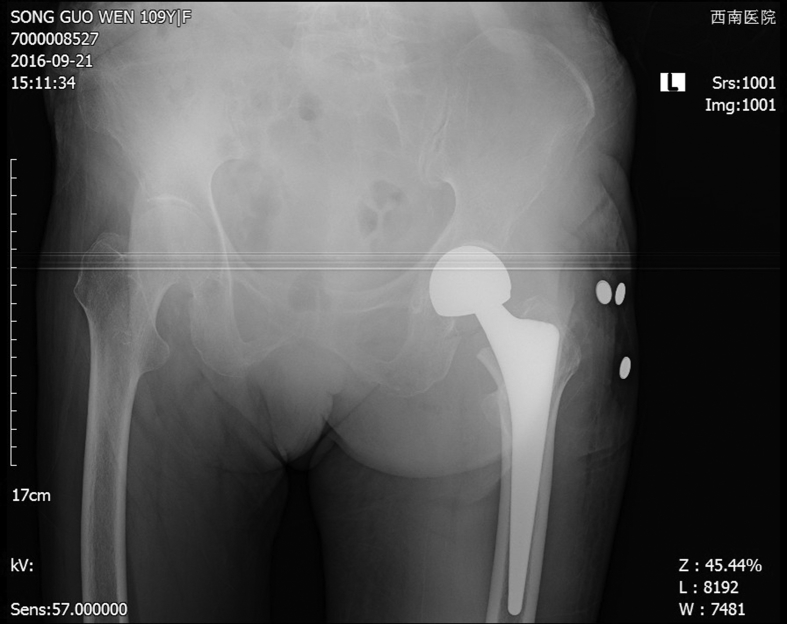

After admission, blood transfusion, intravenous iron supplement, erythropoietin subcutaneous injection and folic acid were offered to correct anemia, the HGB raised to 89 g/L, close to her basic level. We evaluated her basal metabolism by recording the intake and output volume. Hospital consultation was conducted preoperatively, and the related department collaboration and perioperative treatment plan were carefully made. Lumbar plexus, sciatic nerve and the lateral cutaneous nerve block were chosen. Perioperative intravenous infusion speed was controlled under 120 ml/h. And urine output remained at around 30 ml/h. The three dimensions visual template technology and hip fracture model printing ensured accurate measurement and evaluation (Fig. 2). After full preparation, she was offered the left artificial femoral head replacement with lateral position and posterolateral approach. We found that fracture line extended from the great trochanter to the top of the small trochanter with great trochanter avulsion fracture. The femoral neck was cut without dislocation. Then we took out the femoral head, reamed the cavity directly and inserted the implant mold. The fracture was stable, so we put the prosthesis to the fracture position apart from suturing of avulsion fracture (Fig. 3). The operation went smoothly and safely, with about 100 ml bleeding during the operation and 8 cm incision length.

Fig. 3.

Postoperative prosthesis position was good and the fracture end was stable.

The function was good and no special discomfort half years after the operation. X-ray showed the fracture healed completely with the prosthesis in a good position (Fig. 4).

Fig. 4.

The fracture healed completely with the prosthesis in good position half years after the operation.